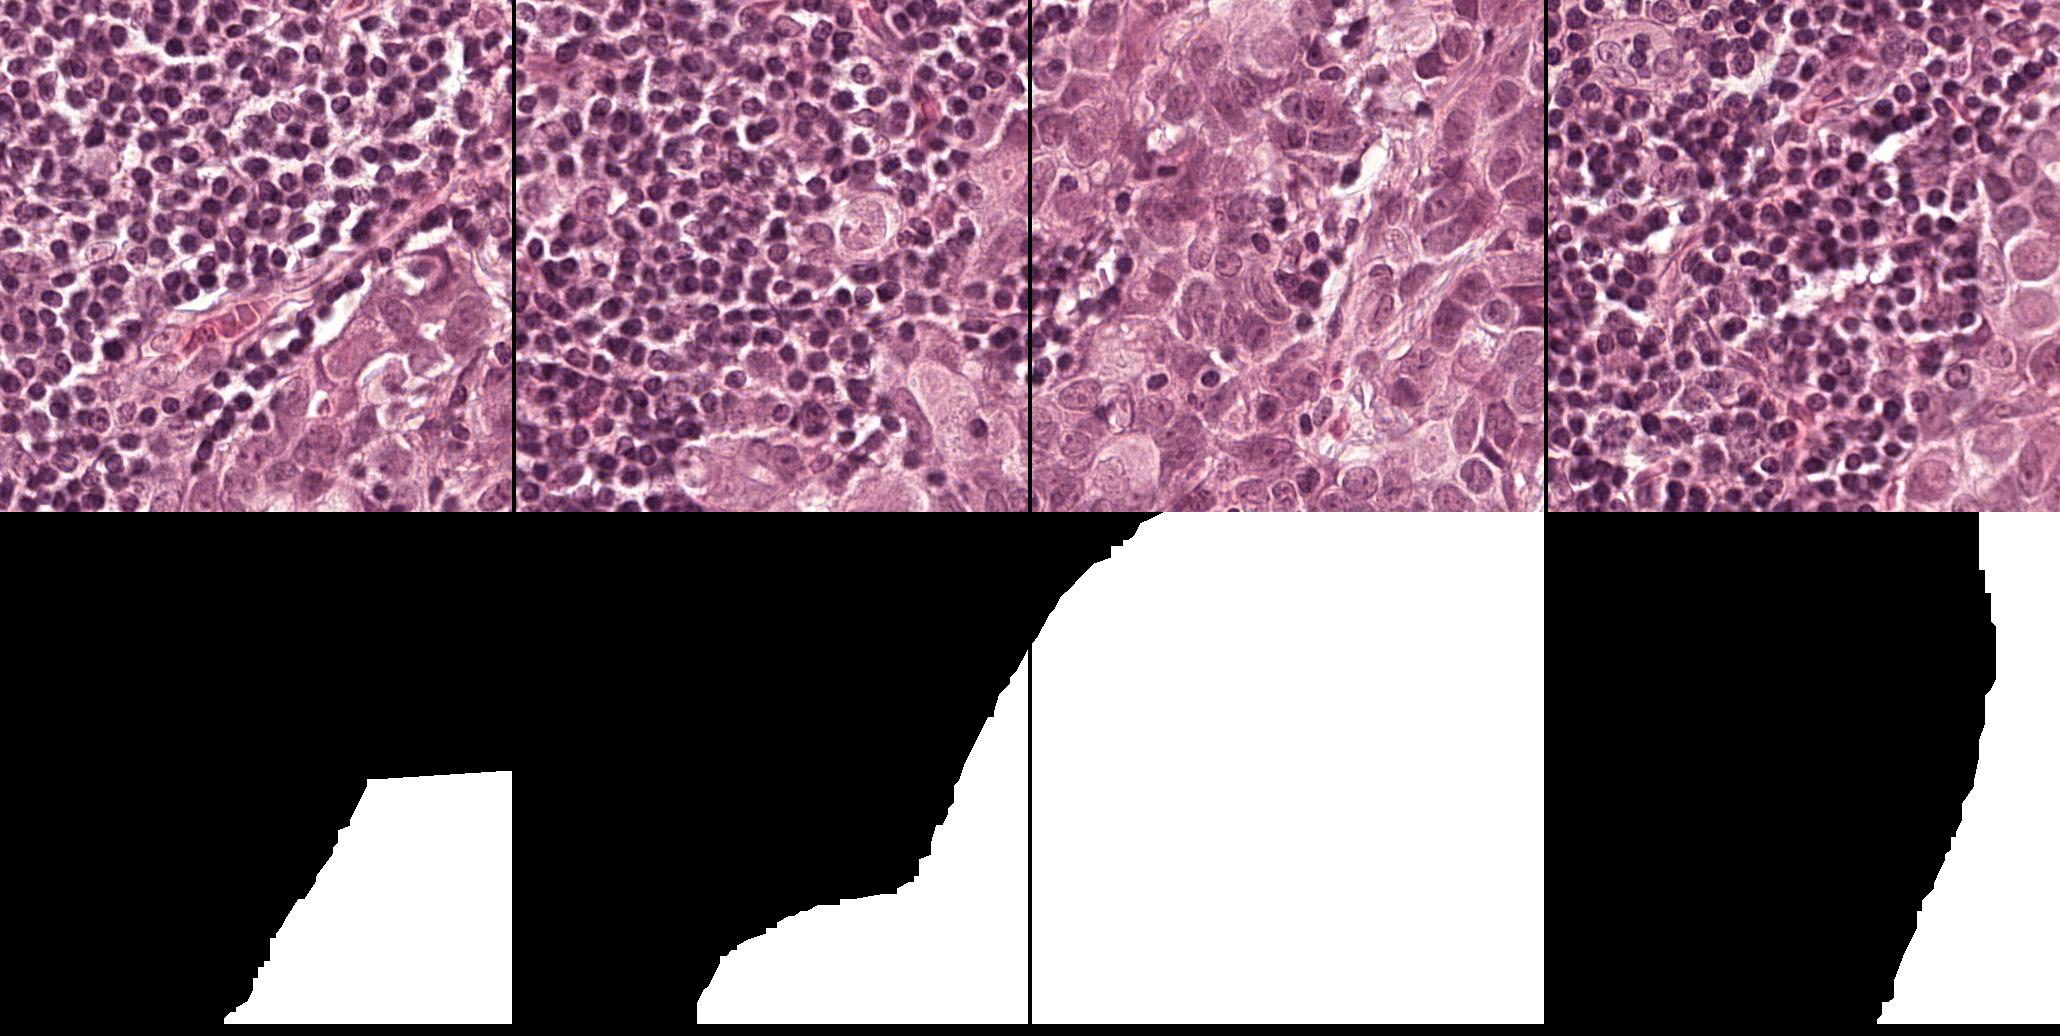

In this section, we describe the two public datasets of histology images used in our experiments: GlaS for colon cancer, and CAMELYON16 for breast cancer.

3.3.1 GlaS dataset (GlaS)

This is a histology dataset for colon cancer diagnosis (Sirinukunwattana et al., 2017)444The Gland Segmentation in Colon Histology Contest: https://warwick.ac.uk/fac/sci/dcs/research/tia/glascontest. It contains 165 images from 16 Hematoxylin and Eosin (H&E) histology sections and their corresponding labels. For each image, both pixel-level and image-level annotations for cancer grading (\ie, benign or malign) are provided. The whole dataset is split into training (67 samples), validation (18 samples), and testing (80 samples) subsets. Among the validation set, 3 samples per class are selected to be fully supervised, \ie, 6 samples in total for B-LOC selection.

3.3.2 Camelyon16 dataset (CAMELYON16)

This dataset555The Cancer Metastases in Lymph Nodes Challenge 2016 (CAMELLYON16): https://camelyon16.grand-challenge.org/Home is composed of 399 WSI for detection of metastases in H&E stained tissue sections of sentinel auxiliary lymph nodes (SNLs) of women with breast cancer (Ehteshami Bejnordi et al., 2017). The WSIs are annotated globally as normal or metastases. The WSIs with metastases are further annotated at the pixel level to indicate regions of tumors. An example of a WSI is provided in Figure 6. Among the 399 WSIs provided, 270 are used for training, and 129 for testing666Sample test_114 is discarded since the pixel level annotation was not provided. Therefore, the test set is composed of samples with samples with nodal metastases.. The large size of the images makes their use in this survey inconvenient. Therefore, we designed a concise protocol to sample small sub-images for WSL with pixel-wise and image-level annotations. In summary, we sample sub-images of size to form train, validation, and test sets, respectively (Fig.7). A detailed sampling protocol is provided in section B. This protocol generates a benchmark containing a total of 48,870 samples: 24,348 samples for training, 8,858 samples for validation, and 15,664 samples for testing. Each sub-set has balanced classes. For B-LOC, we randomly select 5 samples per class from the validation set to be fully supervised, \ie, 10 samples in total.